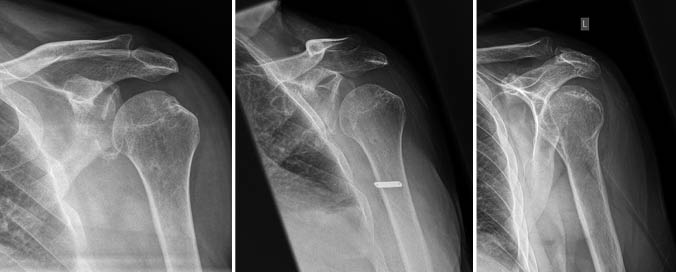

Zur Zusammenhangsbegutachtung steht der Fall eines Versicherten, welcher eine arbeitsunfallbedingte persistierende hintere Schulterinstabilität links bei berufsgenossenschaftlich anerkannter Vorerkrankung am Schultergelenk erlitt. Berichtet wird über die medizinische Behandlung und...